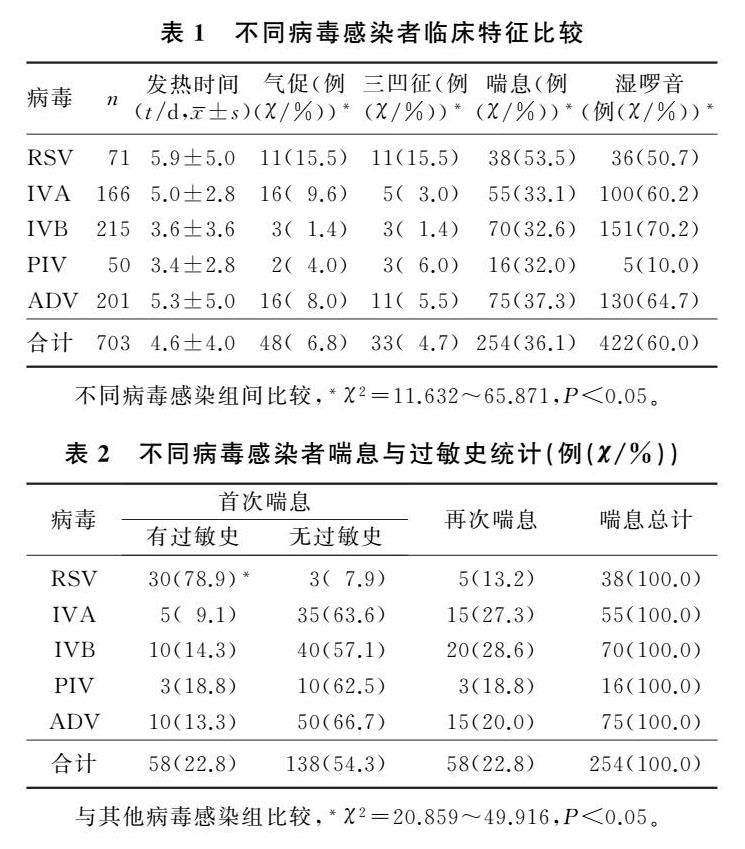

论著 | 儿童病毒性肺炎703例临床分析

论著 | 儿童病毒性肺炎703例临床分析